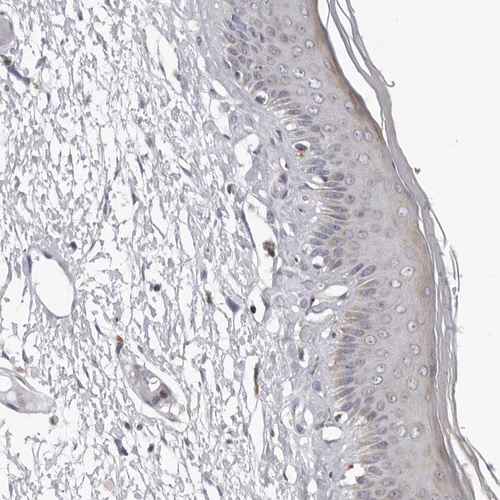

Immunohistochemistry analysis in human liver and skin tissues using HPA028202 antibody. Corresponding CPT2 RNA-seq data are presented for the same tissues.